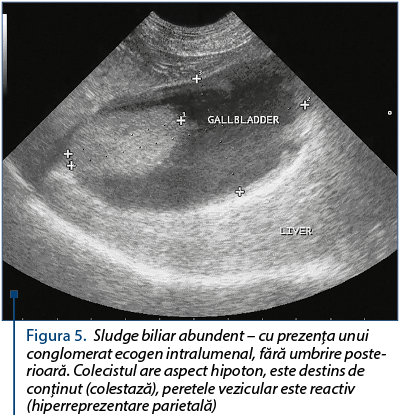

Aspecte ecografice ale sludge-ului biliar: aspect ecografic stratificat, bila îşi pierde aspectul omogen transsonic (anecogen), bila capătă ecogenitate prin prezenţa elementelor corpusculare care îi dau ecogenitate proprie (figura 3 şi figura 4), dar fără umbrire posterioară. Pot apărea chiar elemente inframilimetrice (de 2-3 mm), care se pot deplasa sincron cu cinetica respiratorie sau la presiunea cu sonda ecografului (figura 5 şi figura 6).

Figura 5. Sludge biliar abundent – cu prezenţa unui conglomerat ecogen intralumenal, fără umbrire poste­rioa­ră. Colecistul are aspect hipoton, este destins de con­ţinut (colestază), peretele vezicular este reactiv (hiperreprezentare parietală)